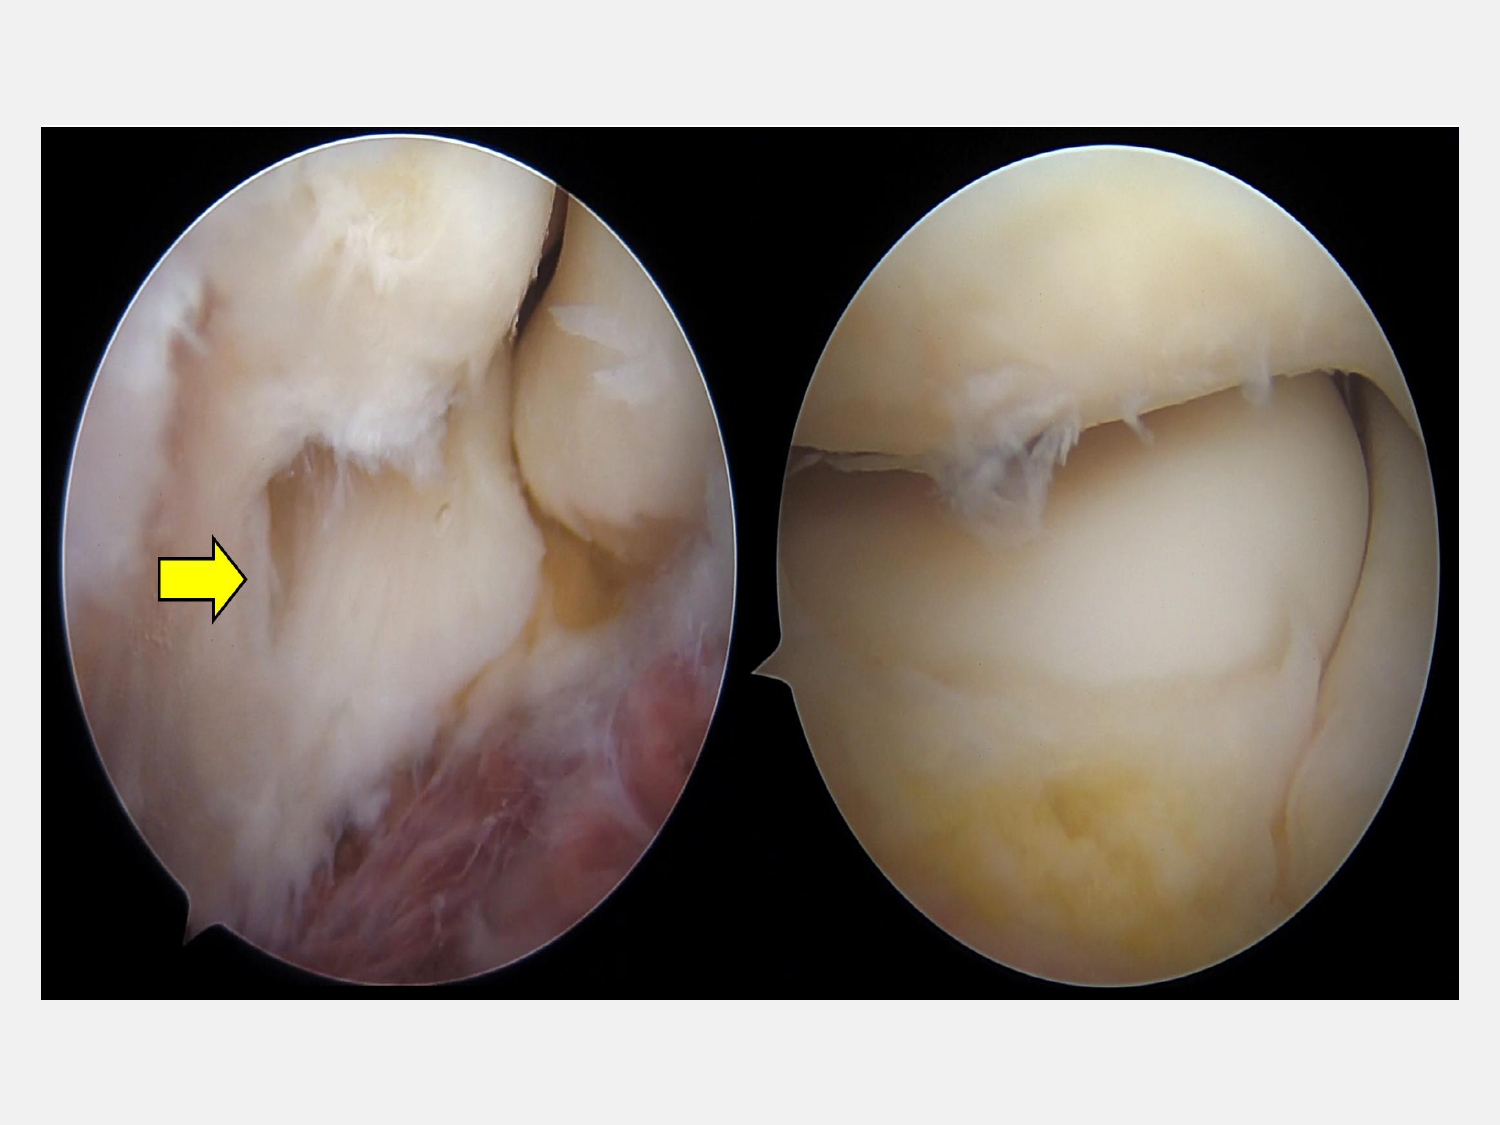

陳重宇醫師表示,C小姐經理學檢查及核磁共振(MRI)後發現,除了肱骨外上髁炎外,還合併肘關節滑膜皺襞增生與軟骨軟化。這類結構性病因若僅以「網球肘」的治療方式處理,往往難以根治。

陳重宇醫師說,外側手肘疼痛並非全是「網球肘」,其他常見原因包括:韌帶或關節囊損傷、剝離性軟骨炎、骨刺或退化性關節炎、滑膜皺襞症候群(synovial plica syndrome)和神經壓迫性疼痛。針對手肘的結構性病因,微創關節鏡手術是一個安全且效果良好的選擇。以C小姐為例,手術透過關節鏡直接觀察肘關節內部結構,精準鬆解發炎的肌腱附著點,並清除增生的滑膜皺襞。手術僅需數個約1公分的小切口,創傷小、出血少,術後疼痛明顯減輕,復原速度快。